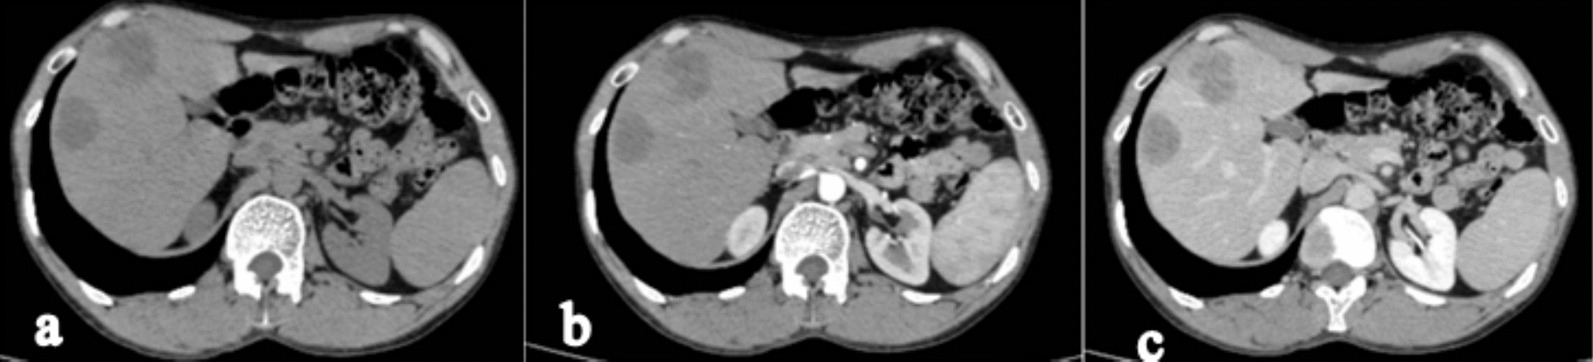

The CECT axial section of the abdomen shows two hypoenhancing lesions in segments VI and VIII of the liver, the largest of which is 3.8 × 4 cm in size in segment VIII, suggestive of metastasis in the liver (Fig. 4a–c). However, a positron emission tomography scan was not done.

Fig. 4.

The contrast enhanced computed tomography axial section of the abdomen (a Plain, b arterial phase c venous phase) shows two hypoenhancing lesions in segment VI and VIII of the liver, the largest of which is 3.8 × 4 cm in size in segment VIII, suggestive of metastasis in the liver